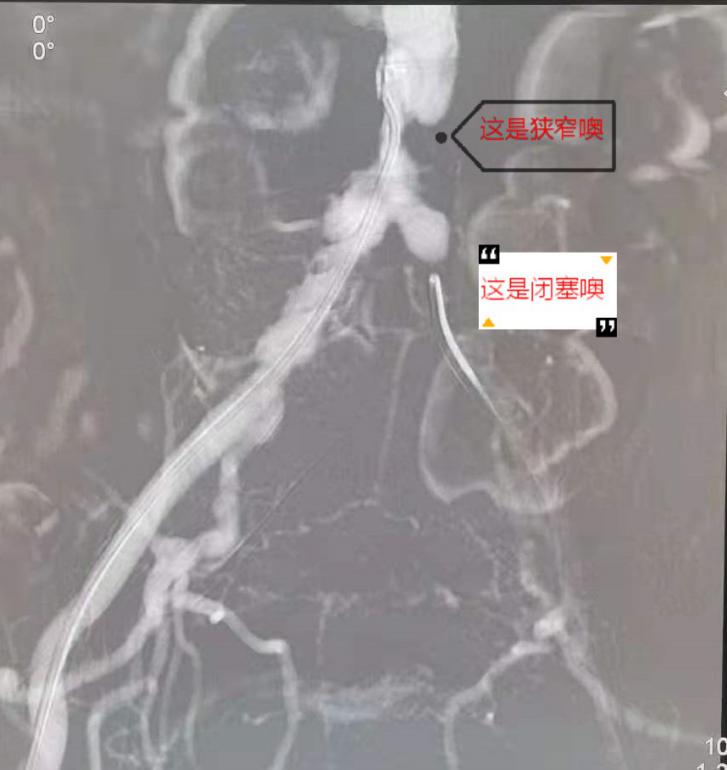

5月20日下午,心脏大血管外科副主任医师唐开维与科室副主任轩永波顺利为老张完成了手术。术中造影提示老张左髂总动脉闭塞,局部多发斑块,无血流通过。腹主动脉下段狭窄约80%,右髂总动脉中上段有斑块,造成局部狭窄50- 60%,左髂总动脉起始部后闭塞。老张病情复杂,两位专家先从左侧多次尝试使导丝导管突破闭塞段,最后成功突破进入腹主动脉真腔内。考虑老张局部动脉斑块多,为预防破裂,他们进行逐级扩张,定位良好后释放支架。为处理老张腹主动脉下段狭窄的问题,他们沿左侧、右侧导丝同时送入血管支架,使用Kissing技术成功释放两枚支架。手术很成功,再次造影时显示老张体内支架位置良好,其内血流通畅,支架无明显狭窄。

(图片3:术中造影显示狭窄和闭塞的血管)